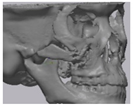

2.2. Computer-Aided Virtual Surgery, Design, and Fabrication of Patient-Specific Devices

2.3. Surgical Procedure